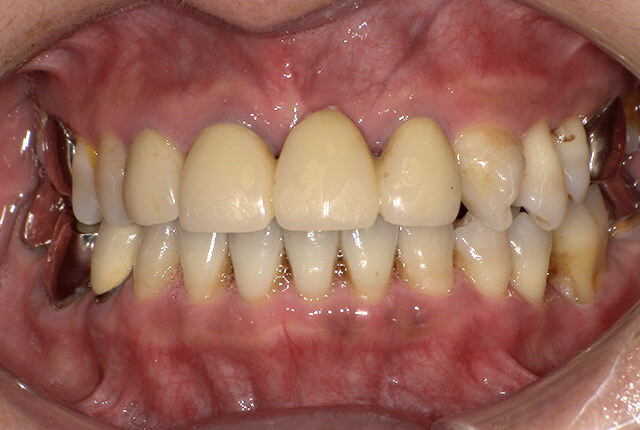

よく噛めず笑うと銀歯が目立つので気にされていました。

90分の治療で銀歯の状態からキレイな状態になります。噛み合わせの調整や審美面も使用しながら合わせます。

良く噛めて安心と、ご満足いただき大変嬉しく思います。笑顔も一層素敵になりました。

| 主訴 | ブリッジ脱離、しっかり噛めない |

| 診査診断 | 上顎歯牙欠損、歯周病、不良補綴、根尖性周囲炎。 不正咬合により噛み合わせのバランスが悪い事が原因により咬合治療が必要。 |

| 治療内容 | 欠損部インプラント 不正咬合に対し不良補綴のやり直しと合わせて咬合再構築 |

| 治療期間 | 4ヶ月 |

| 費用 | 200万円 |